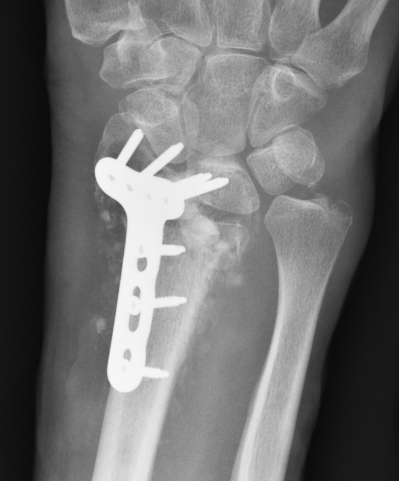

Undisplaced wrist fracture

- interrupts blood supply at a watershed area

- between 3 weeks and 3 months post injry